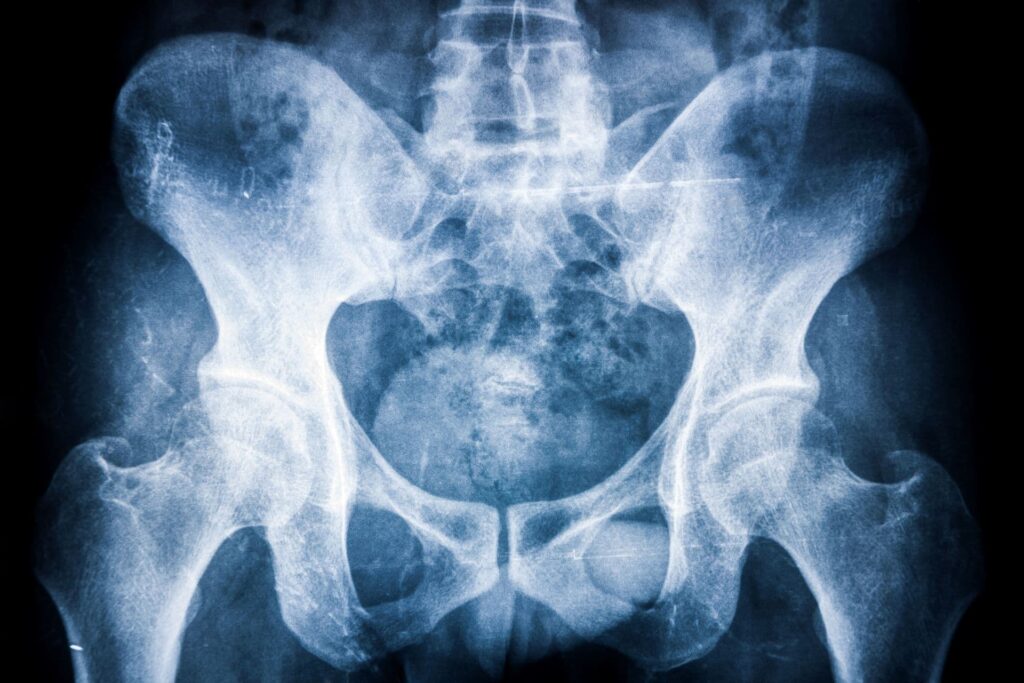

Bechterew-kór (spondylitis ankylopoetica) tünetei és kezelése

A Bechterew-kór (spondylitis ankylopoetica) elsősorban a gerinc ízületeket, illetve a medencecsont és a keresztcsont között található ízületeket érintő gyulladásos betegség, amely idővel akár az alsó…